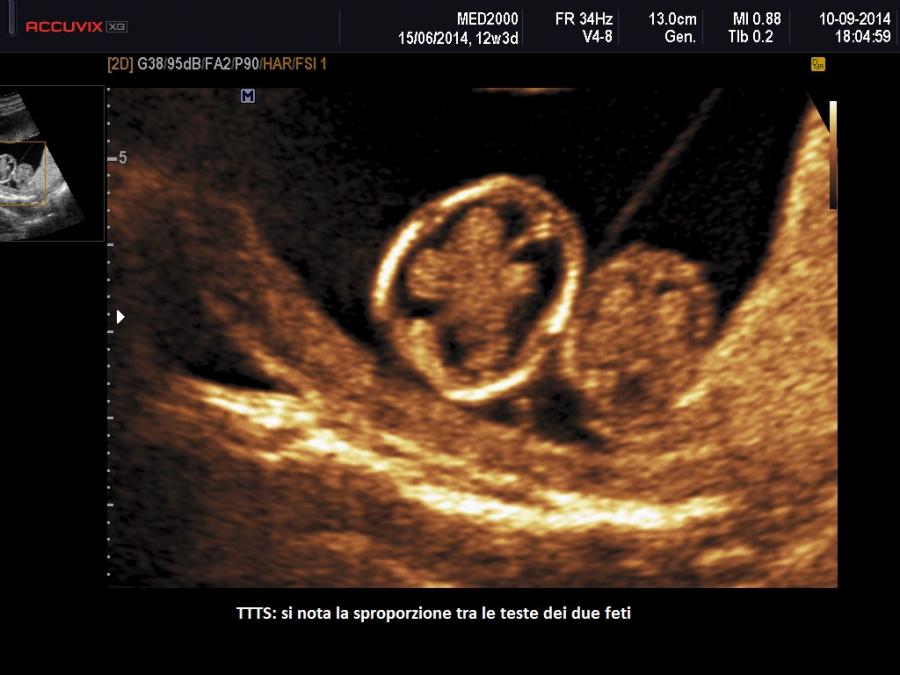

A 11-14 settimane si sospetta una TTTS quando: